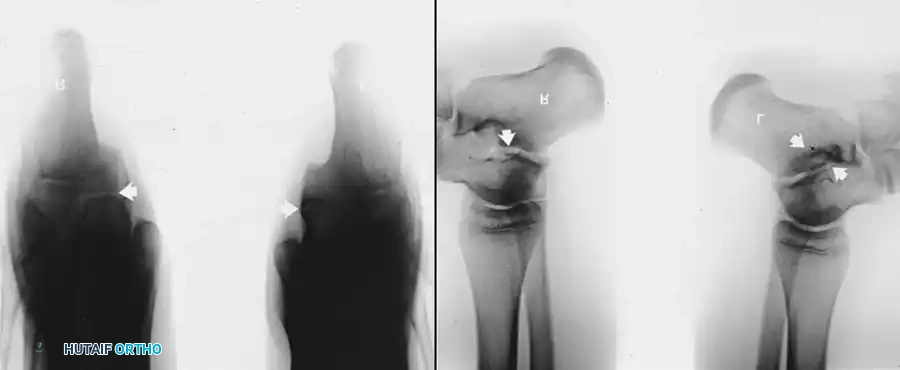

Radiographic Imaging

The 45-degree lateral oblique radiograph is the gold standard for diagnosing a calcaneonavicular coalition. The abnormal bar extends from the anterior process of the calcaneus (just lateral to the anterior facet) dorsally and medially to the lateral/dorsolateral extra-articular surface of the navicular. It typically measures 1 to 2 cm in length and 1 to 1.2 cm in width.

In incomplete coalitions, the adjacent bony margins appear irregular, sclerotic, and indistinct. The talar head may also appear small and underdeveloped.

While standard anteroposterior and lateral radiographs may show secondary signs (such as the "anteater nose" sign for calcaneonavicular coalitions or the "C-sign" and talar beaking for talocalcaneal coalitions), advanced imaging is often utilized in modern practice.

Advanced Imaging and Anatomical Reference Gallery

The following images illustrate various presentations, surgical exposures, and advanced imaging modalities (including CT and MRI correlates) utilized in the comprehensive evaluation and treatment of rigid pes planus and tarsal coalitions: